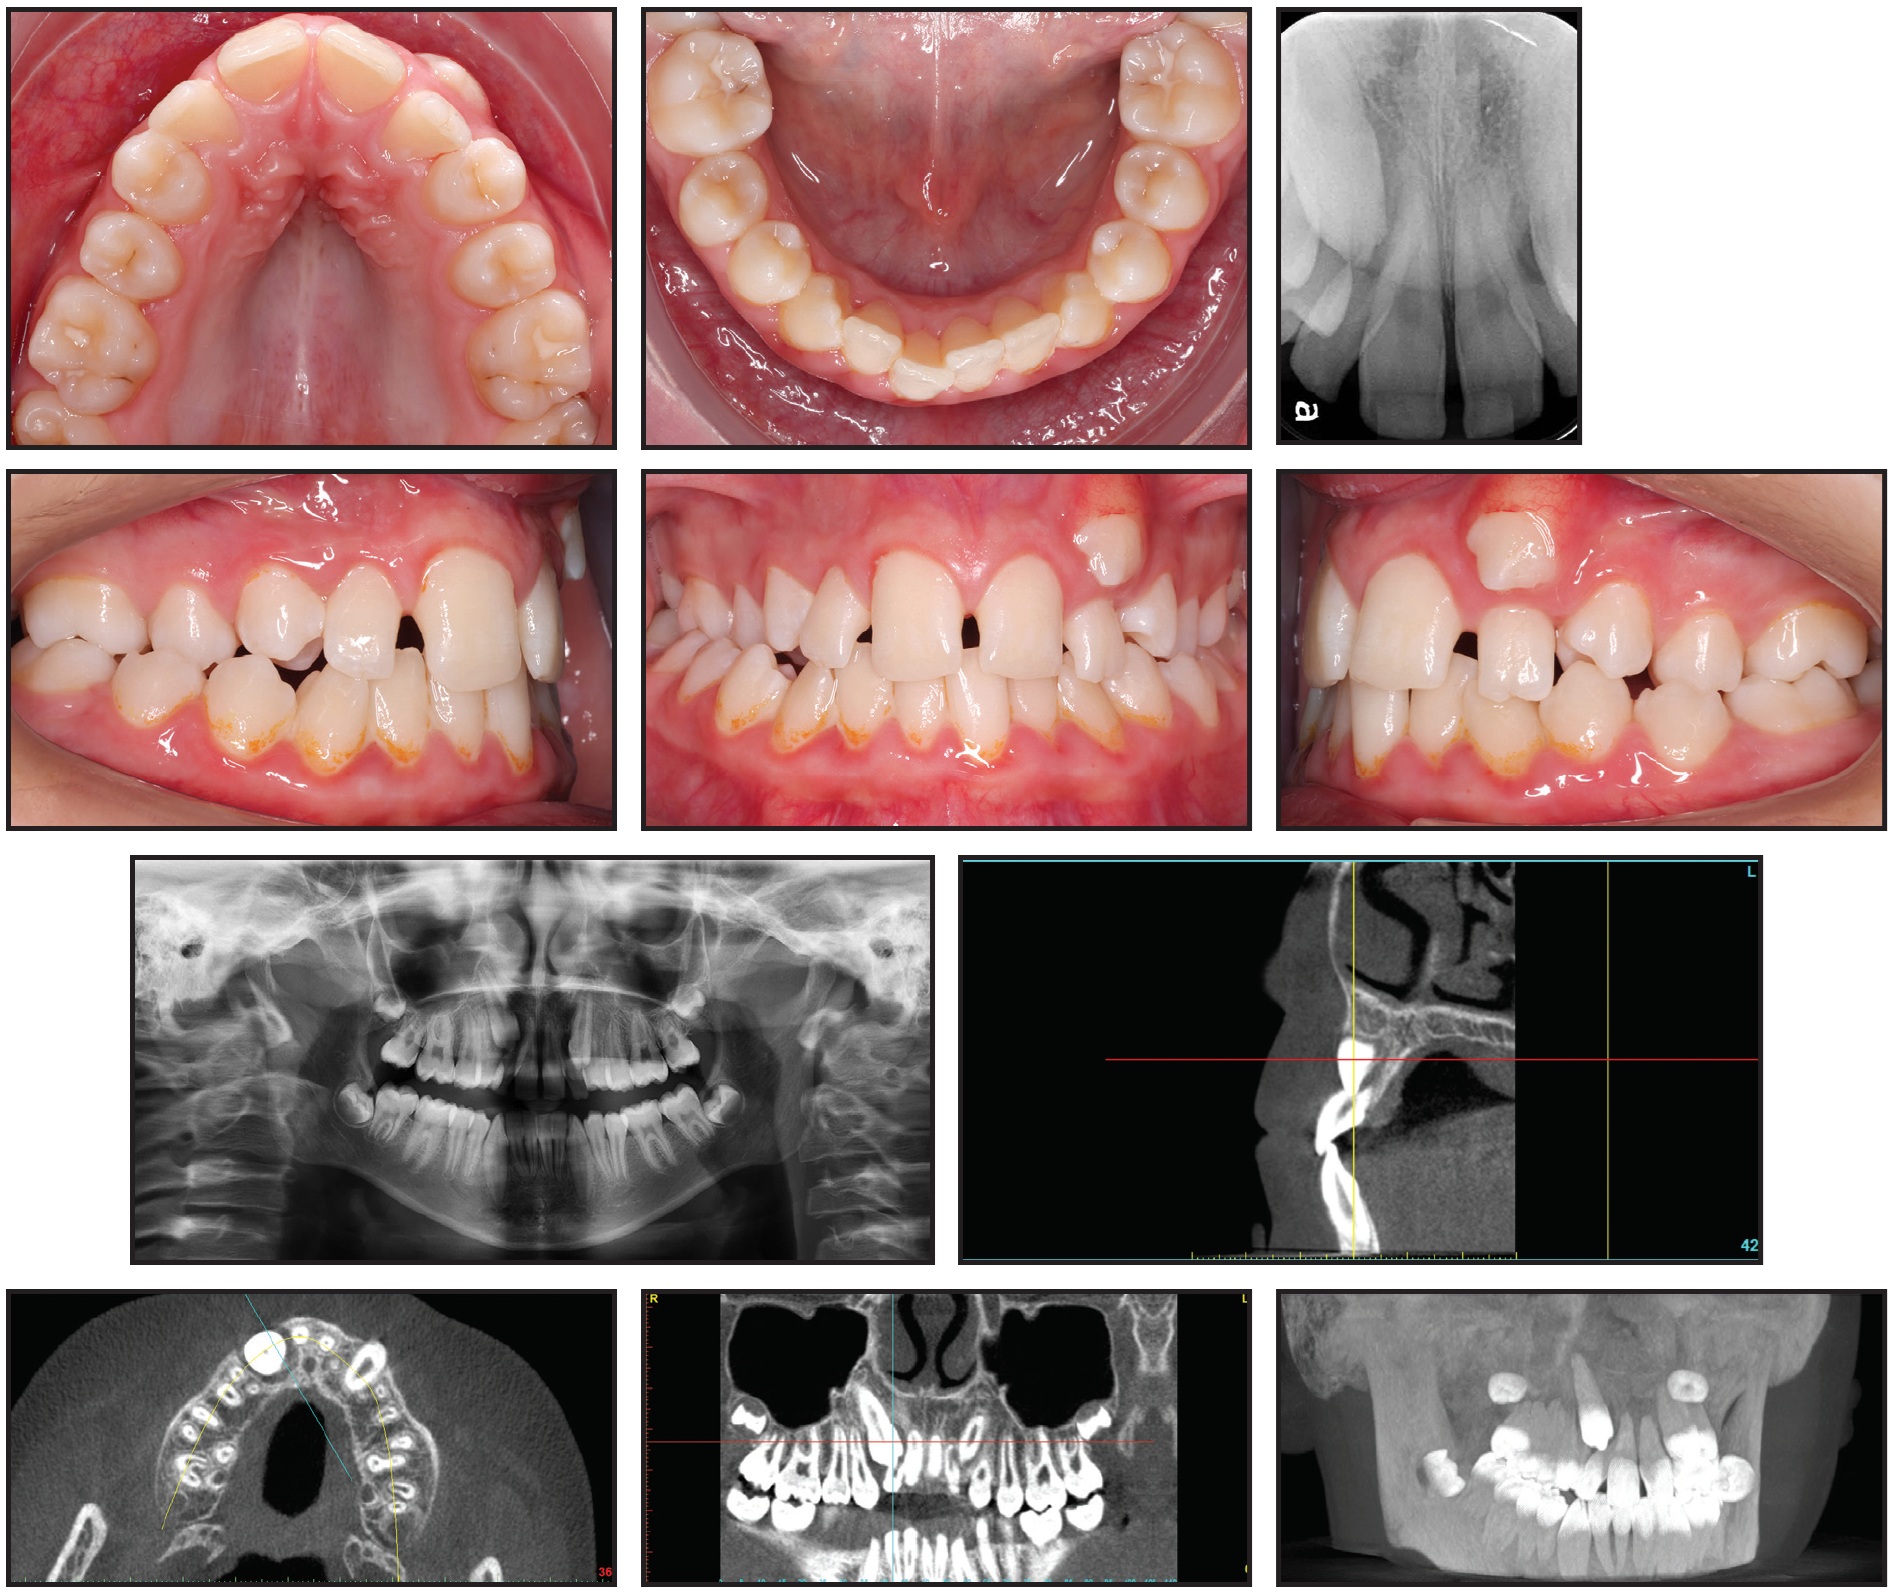

A 13-year-old male presented with a mild dental Class II malocclusion, a bilateral crossbite (upper right first premolar through second molar to lower right first premolar through second molar, and upper left second premolar to lower left second premolar), and a functional shift of the mandible to the right (Fig. 1).

Fig. 1 Case 1. 13-year-old male with mild dental Class II malocclusion, Class I skeletal pattern, and upper and lower crowding before treatment. (Position of upper right canine and integrity of upper lateral incisor roots not apparent on standard x-ray images.)

Clinical examination indicated a Class I skeletal pattern, maxillary constriction, and 9mm of crowding in the upper arch, with a lack of space for the canines; the lower arch showed moderate crowding (5mm). The left maxillary canine had partially erupted in an ectopic position, buccal to the upper left lateral incisor. The upper lateral incisors were buccodistally tipped, and the upper right canine was not palpable buccally or palatally.

The initial evaluation would likely have led to a nonextraction treatment plan including maxillary expansion and some form of arch development to resolve the crowding in both arches and gain enough space for the canines to erupt. There was, however, a radiographic suggestion of root resorption involving both upper lateral incisors. Because the panoramic and periapical x-rays could not clearly confirm the position of the upper right canine nor the integrity of the upper lateral incisor roots, the patient was sent for a CBCT scan.

The DICOM file of the scan was uploaded to the CephX web viewer for automated AI conversion to STL. A 3D segmented model of the teeth and jaws could then be viewed, and the canines and central incisors could be virtually extracted for better visualization of the lateral incisors (Fig. 2).